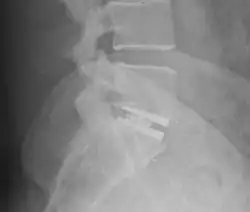

Die Abbildung zeigt einen Zustand nach Spondylodese der zwei untersten Lendenwirbelkörper (LWK4 und LWK5) mit dem ersten Sakralwirbel (SWK1) zwei Jahre nach der Operation. Der Zwischenwirbelraum zwischen dem vierten und dem fünften Lendenwirbelkörper ist bereits knöchern überbrückt (ankylosiert); beim Übergang vom fünften Lendenwirbelkörper zum ersten Sakralwirbel fehlt diese knöcherne Durchbauung. Wenn alle verblockten Wirbelkörper stabil knöchern miteinander verbunden sind, kann das Spondylodesematerial entfernt werden.

Dorsoventrale Spondylodese LWK5 – SWK1 -

Der gleiche Patient in der MPR -

Die Pfeile zeigen die knöcherne Durchbauung LWK4/5 und die fehlende Durchbauung LWK5/SWK1 an. -